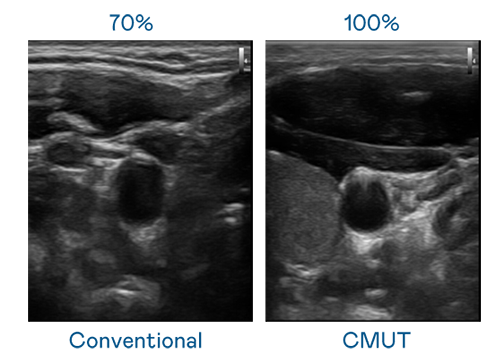

CMUT 技术是一种用电容式微机电元件来产生超音波讯号的技术。与传统 PZT 压电式技术相比,CMUT 频宽增加 30%,更宽频的超音波讯号让影像解析度大幅提升,是实现高影像品质医疗超音波扫描、促进精准医疗发展的关键技术。

超音波影像的解析度高低,首先取决于探头能发出的讯号频宽。mg冰球突破 CMUT 可提供高清晰的超音波讯号,提供高频宽、高灵敏度、影像纹理细节更高的超音波影像,协助医护人员缩短影像判读时间及利用精准的医疗影像进行诊断。